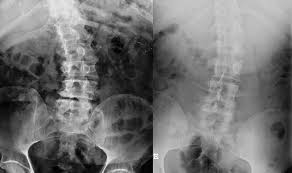

1. First Degree – the spine deviates to the side up to 10 degrees, twisting is not visually determined, but can be seen on the picture;

– the presence of a small hump, the spine is curved to one side at an angle of up to 25 degrees, which is clearly visible both on the x-ray and with the naked eye;

3. Third Degree – a large hump is formed, the spinal column is bent at an angle of up to 40 degrees;

4. Fourth degree

– the figure is disfigured, a hump appears on the ribs, the pelvic bones and chest are deformed, angle of curvature up to 90 degrees.